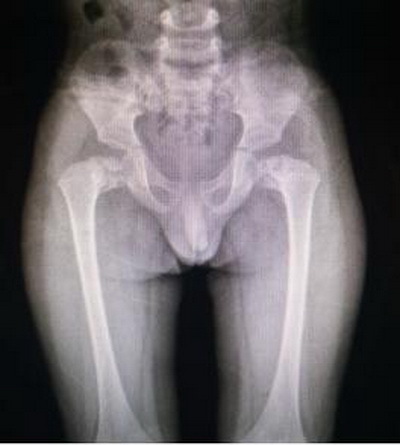

曲敬主任介绍,髋关节内翻畸形就是股骨颈轴线和股骨干轴线之间形成一个内倾角,或称颈干角。正常值在110-140度之间。颈干角大于正常值为髋外翻,小于正常值为髋内翻。先天性髋内翻亦称发育性髋内翻,系幼儿时发生的股骨颈干角进行性减小所致的畸形。正常成人的颈干角为120deg;~140deg;,儿童为135deg;~145deg;。若颈干角小于120deg;,称为髋内翻。表现为日见加重的跛行,是小儿跛行常见原因之一。而患儿PHILIP双侧髋关节颈干角经过曲敬教授团队三维重建后精确测量为左侧108°,右侧104°。

术前双髋关节正位片